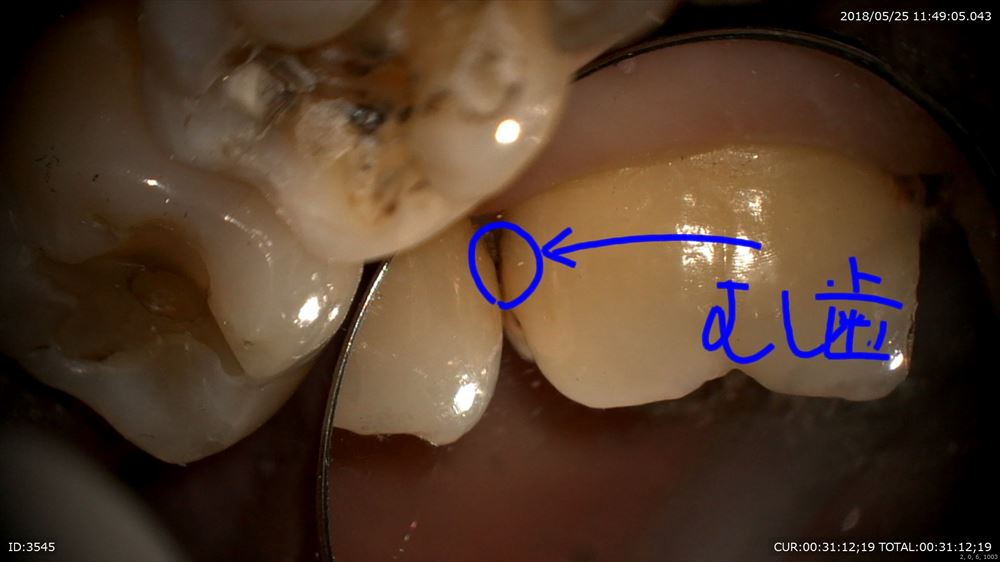

ほら。患者さまにもこの画像を見て頂き

ここを拡大。クラック見てみましょう。20倍

この様に虫歯はクラックからも発生します。